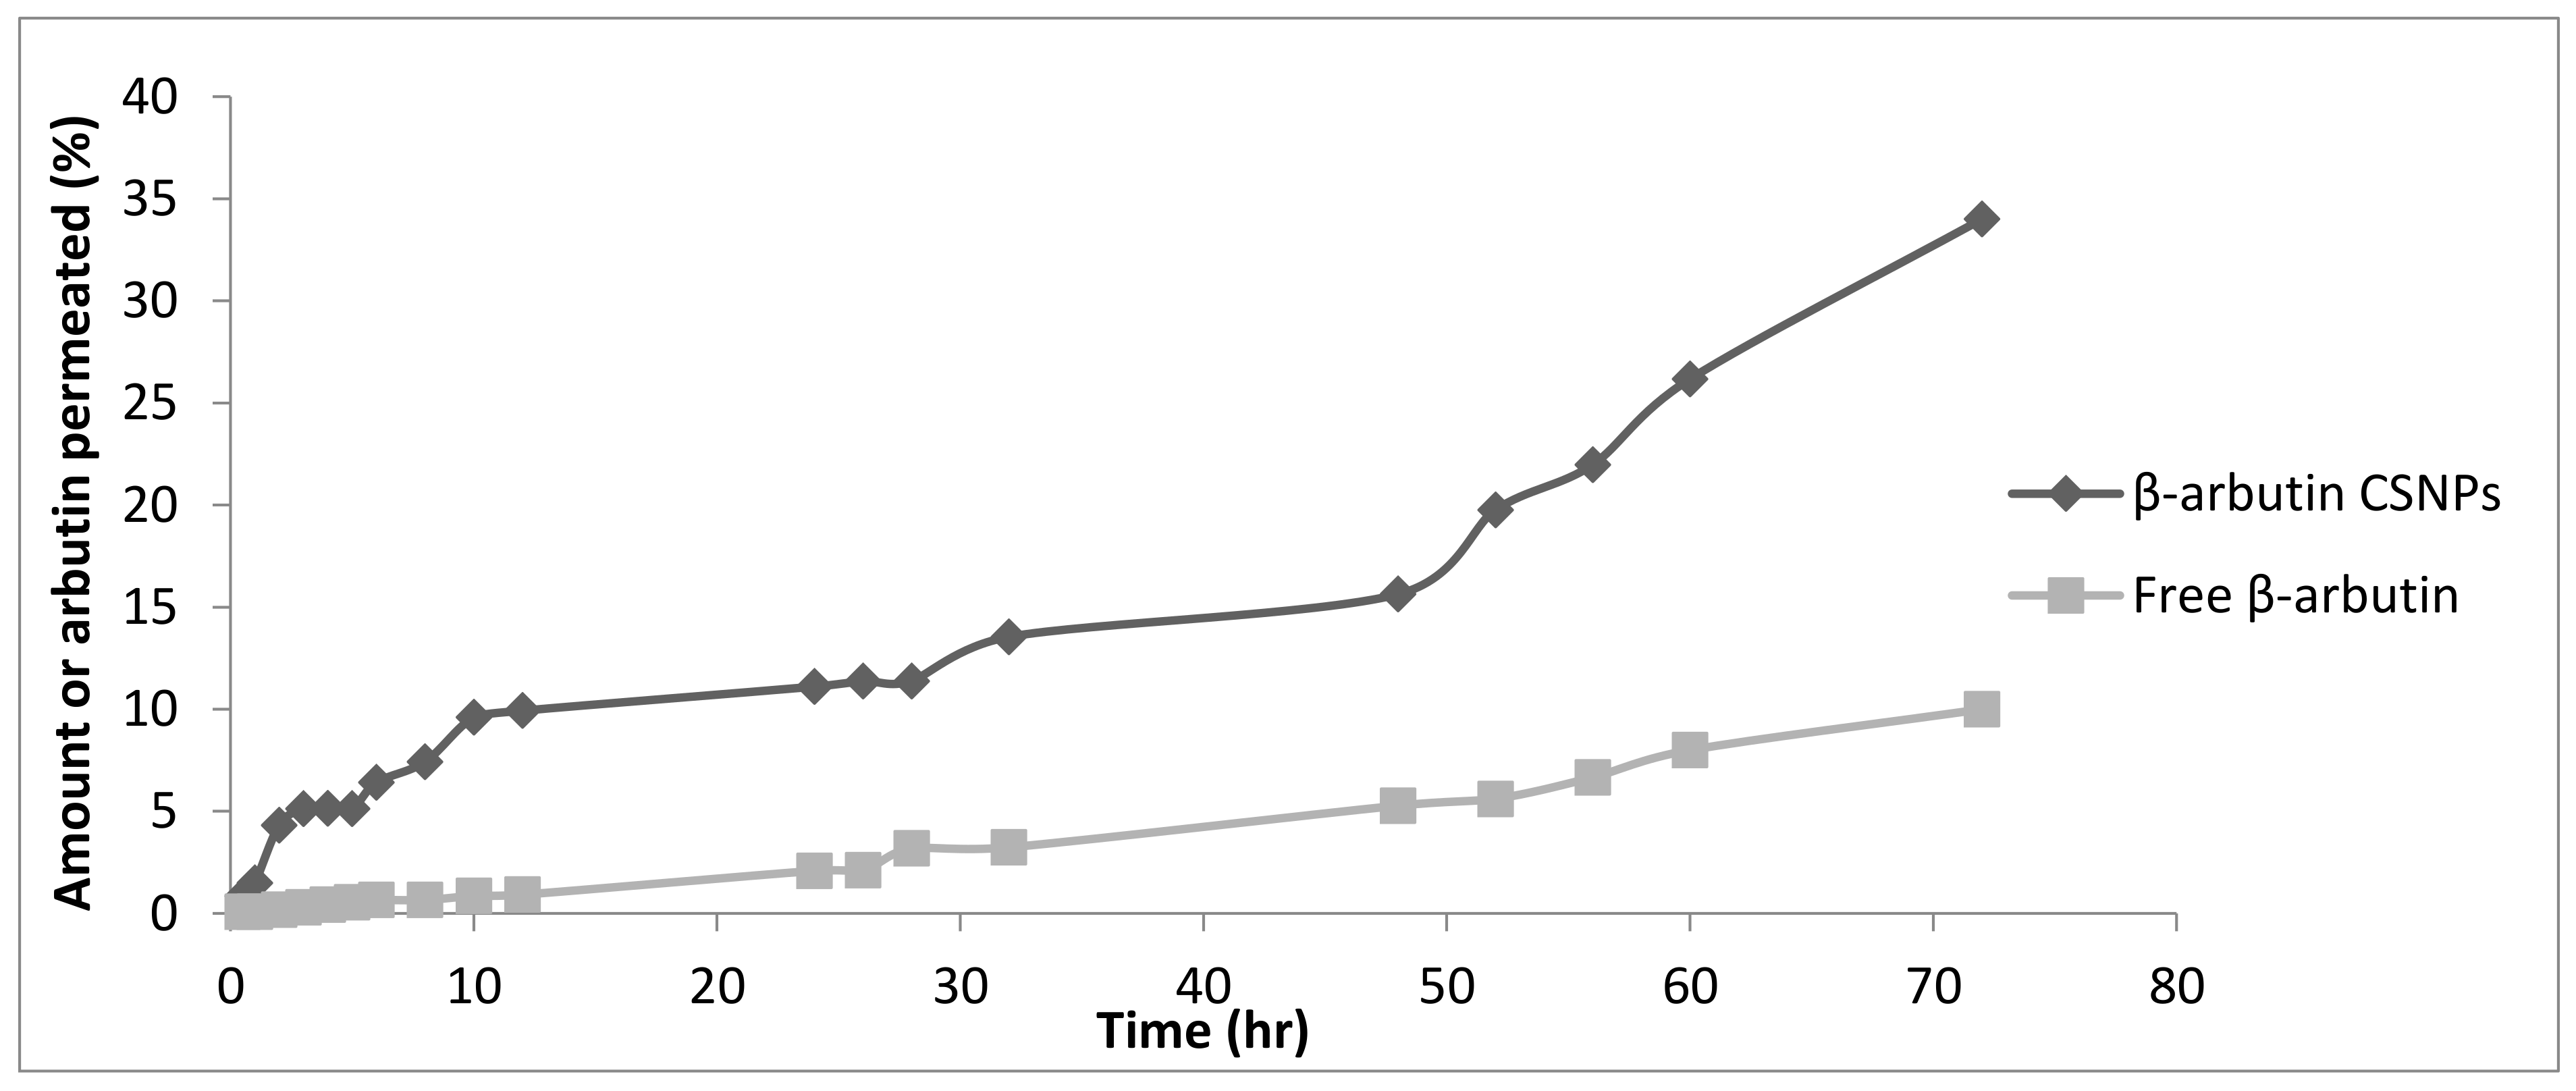

3.7. In Vitro Permeation Study